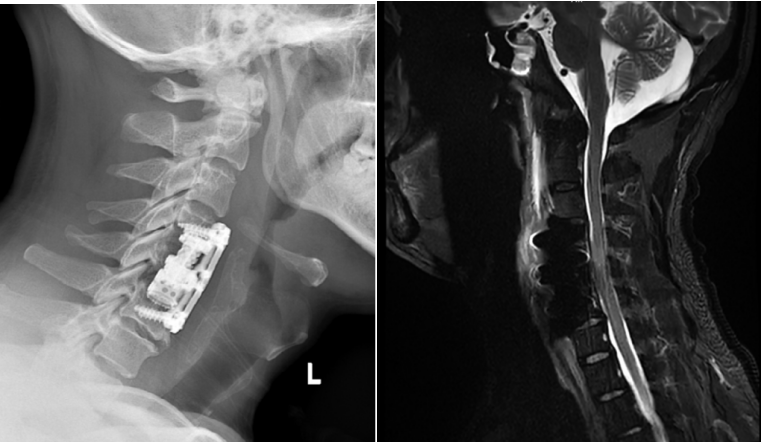

手術(shù)后患者X光及核磁共振復(fù)查

“手術(shù)核心操作用了不到一個(gè)小時(shí),新型錐體植入完成后,X光報(bào)告人工椎體安得非常好,整個(gè)手術(shù)室都響起了掌聲?!必?fù)責(zé)此次手術(shù)第二助手的蔣奎軍醫(yī)生回憶起當(dāng)時(shí)的場(chǎng)景,仍難掩激動(dòng)。